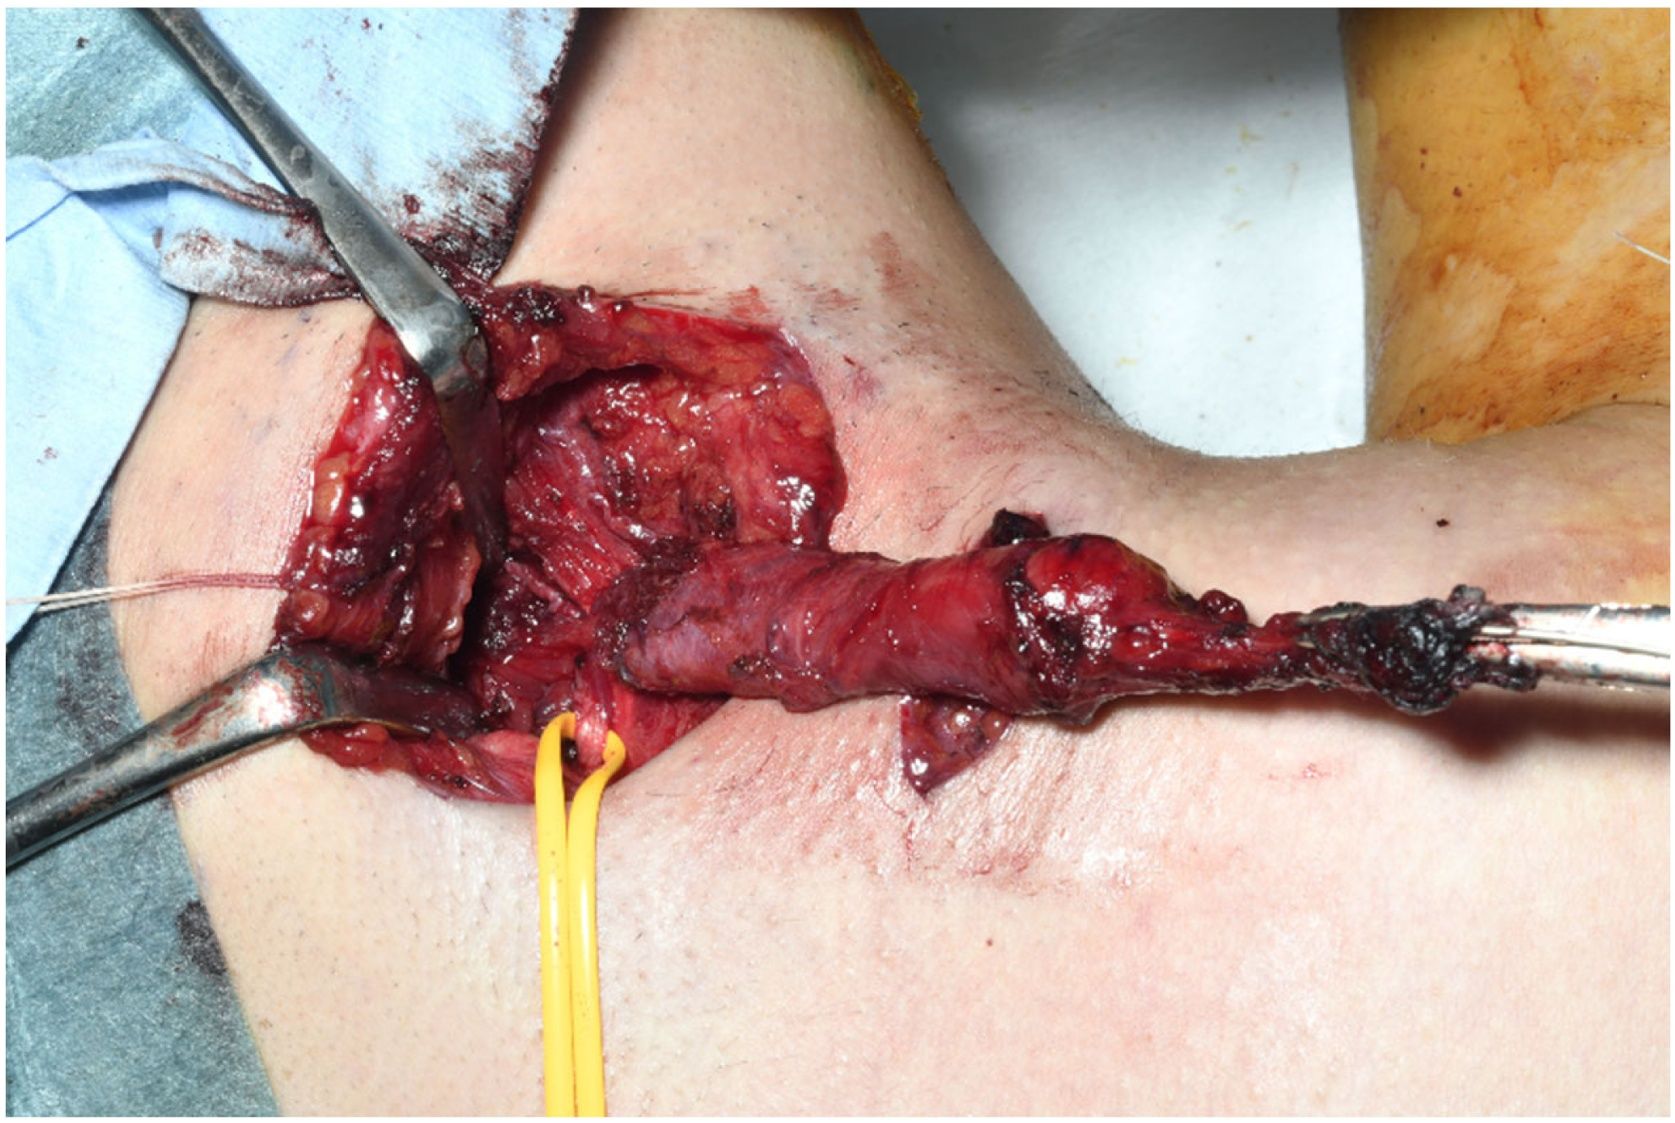

The tract was excised under general anaesthesia. Indigo carmine injection into the cannulated cervical orifice resulted in dye leakage from the tongue root. A parallel skin incision, an elliptical incision around the cervical orifice, and a 7-cm transverse skin incision at the level of the hyoid bone were made. The skin flap was elevated under the platysma muscle, and the fistulous duct was dissected upward from the surrounding tissue. The tract strayed under the anterior belly of the digastric muscle and extended through the anterior end of the submandibular gland and superficially to the hypoglossal and lingual nerves. At the tongue root, the tract, which was tapered and branched (Fig. 3), was ligated under the right oral floor mucosa between the sixth and seventh tooth from the midline and then excised. The submandibular gland and fistulous tract were not connected. Finally, the surgical field was thoroughly rinsed with saline solution, a drainage tube was placed, and the wound was sutured.

Cervical parallel skin incisions. An elliptical incision around the cervical orifice and a 7-cm transverse skin incision at the level of the hyoid bone are made. The fistulous duct is dissected upward from the surrounding tissue, appearing to taper and branch at the tongue root. A yellow vascular tape is applied over the hypoglossal nerve.